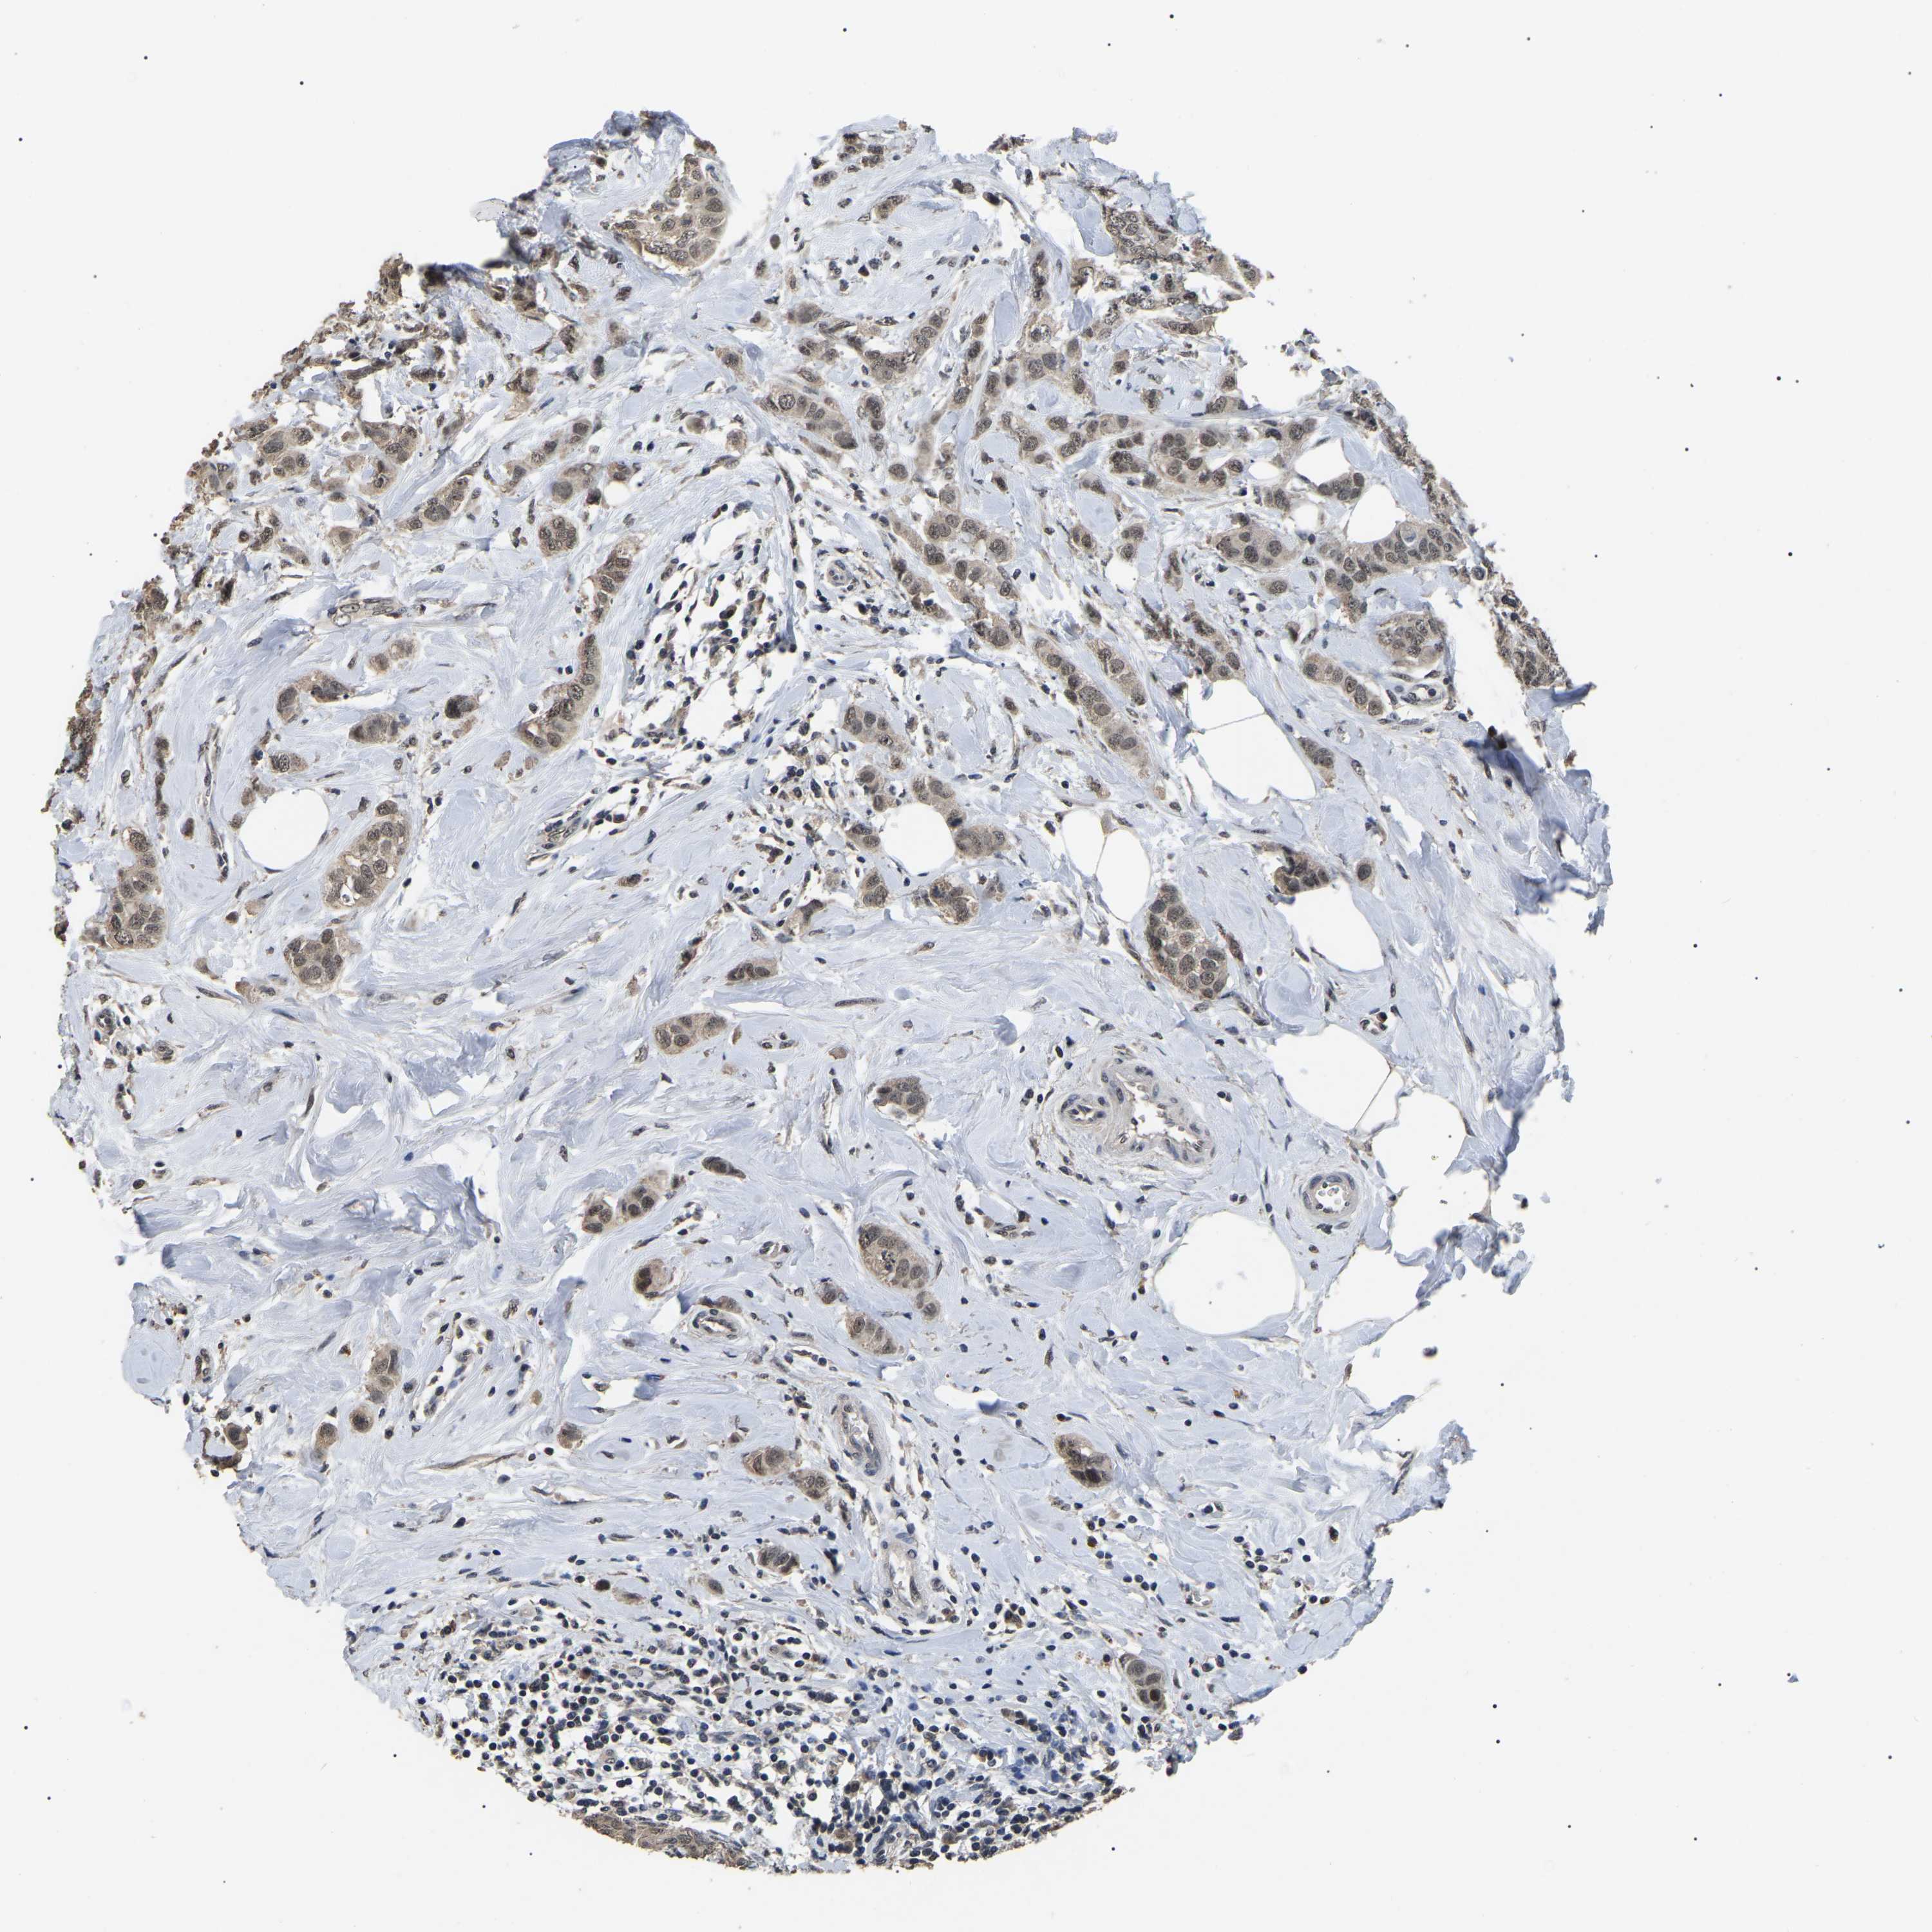

CANCER BREAST CANCER Show tissue menu

BRCA TCGA BRCA VALIDATION PROTEIN EXPRESSION